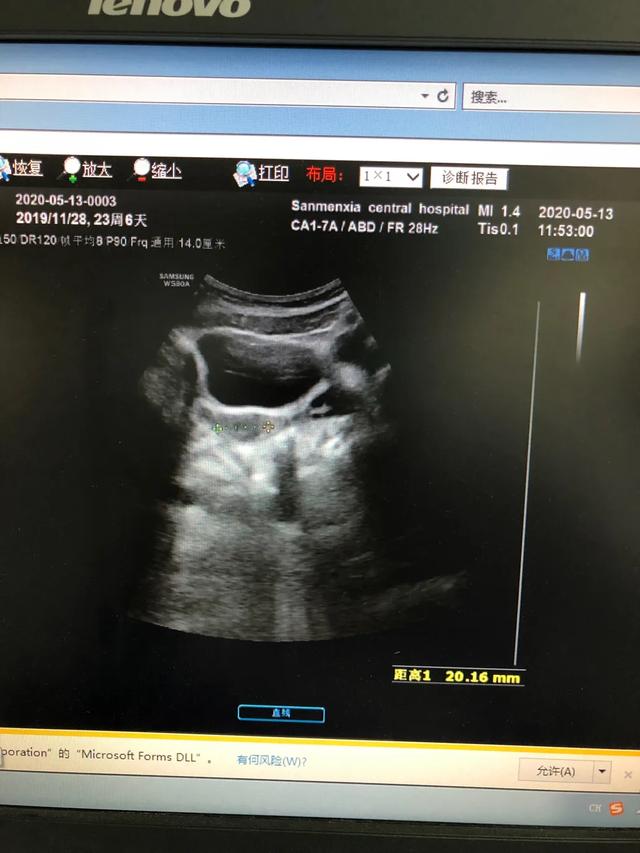

下图是一例患儿性早熟的B超结果、胸片结果及血清学化验结果。

从检查结果来看,B超显示子宫卵巢有囊性回声;胸片显示乳腺发育;而血清学指标,促黄体生成素的峰值是13.09,促卵泡的峰值是20.91,LH/FSH=62.60%。